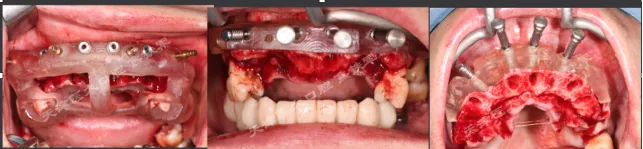

· 上下颌士卓曼360数字化导板 +预成临时修复体设计图。

· 士卓曼360导板包括:骨支持的基部导板 、牙支持的辅助导板 、就位于基部导板的种植导板 以及就位于基部导板的预成临时修复体组成。

· 上下颌计划行即刻种植,各植入六颗straumann钛锆种植体并行即刻修复。

· 下颌士卓曼360数字化序列导板+预成临时修复体

· 上颌360数字化序列导板+预成临时修复体